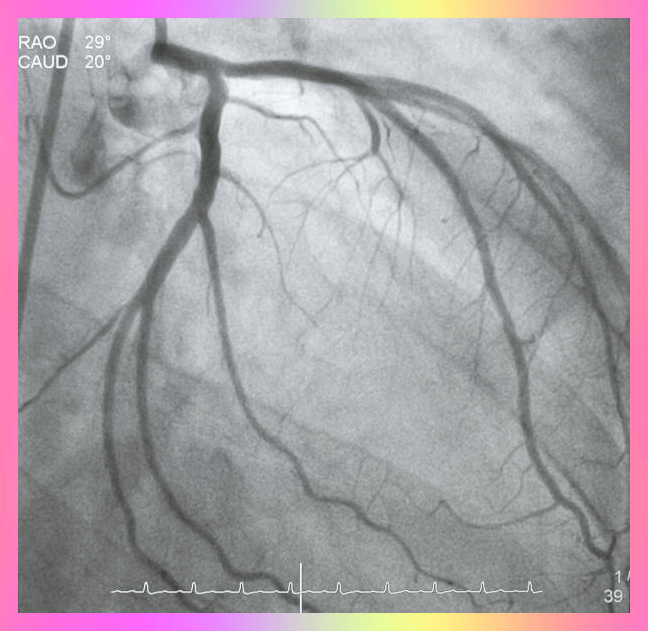

심장마비 관산동맥 질환 - 왼쪽 가슴통증 원인 1

가슴 왼쪽에 통증이 있다면, 심장 마비를 생각 안 할 수가 없습니다. 흉통이 실제로 심장병이나 심장 마비 의 증상 일 수 있지만 항상 그런 것은 아니겠지만 여성은 특히 심장 마비 전에 몇 주 동안 사전 증상이 나타난다는 연구보고를 보면 80% 여성이 심장 마비가 오기 전 4주 전부터 증상을 호소한다고 알려져 있습니다.

왼쪽 가슴 통증은 심장 마비 또는 매 순간 중요한 다른 생명을 위협하는 전조 신호로 알려져 있는데요 설명할 수 없는 왼쪽 또는 중앙 가슴 통증이 있는 경우 병원으로 긴급하게 가셔야 합니다.

협심증 - 왼쪽 가슴 통증 원인 2

협심증은 그 자체로 질병이 아니지만 일반적으로 관상 동맥 심장 질환과 같은 심장 문제의 증상으로 심장근육이 혈액에서 충분한 산소를 얻지 못할 때 생기는 것으로 가슴 통증이나 압박감을 느끼게 되며 주변에 있는 팔, 어깨, 목, 등 또는 턱까지도 증상이 전파된다고 합니다.

협심증 검사가 필요한 경우 진단 테스트를 하면 되는데요 아래와 같은 방법이 있습니다. 그래서 가슴 답답하고 팔과 턱으로 퍼지는 묵직한 통증이 느껴지고 식은땀이 나는 경우는 바로 병원 직을 해서 아래 검사를 받아야 합니다.